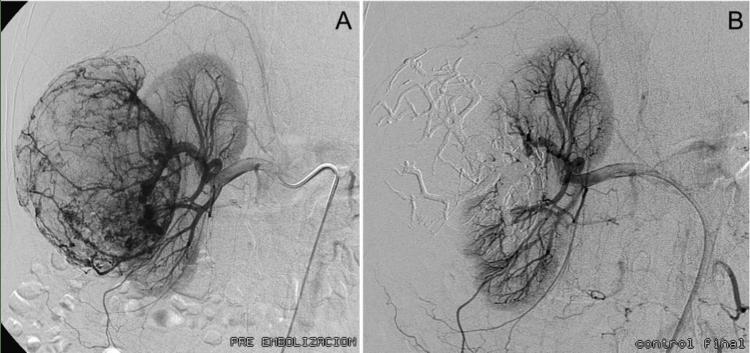

Realizobiopsiadediversosórganosytumo‐res,comosondetiroides,pulmón,hígado, bazo,riñón,páncreas,próstata,hueso.Enel hígadoporejemplopodemosrealizartrata‐mientosdediversostipos,yaseadrenajede quistes,abscesosodelavíabiliarenpacien‐tescontumoresenpáncreas,asícomoderi‐vacionesportosistémicas“TIPS”enpacientes conhipertensiónportalporcirrosis.Lostumo‐resbenignosymalignospuedensertratados medianteterapiasendovascularesembolizan‐doodandoquimioterapialocalatravésdelas arteriasquelellevansangre.

Otraalternativaterapéuticaparaelcáncerde hígadosonlasterapiastermoablativascomo sonablaciónporradiofrecuencia,microondas ocrioablación,quegenerandestruccióndeltu‐mormediantemuertecelularconlaaplicación

Estasúltimastambiénpuedenserutilizadas entratamientodetumorespulmonares.

Lasangiografíasdiagnósticasnosayudana analizarlaanatomíadelasarteriasyvenas quellevanlasangrealosórganos,comolo sonelcerebro,lasextremidadesoelintestino. Enocasionessepuederealizarenunmismo procedimientoeltratamiento,comoangiopla‐stiasenelcasodeestrechezdelasarteriasa niveldelaspiernasoembolizaciones,que consistenentaparelflujodesangrecuando presentamalformacionesenlosvasosoaen pacientesconsangradoactivo,como,por ejemplo,enelintestino.

Paraeltratamientosincirugíadelosmiomas,tu‐morquesepresentaconmayorfrecuenciaenla matrizdemujeresjóvenes,existelaemboli‐zacióndearteriasuterinas.Esteprocedimiento consisteencesarelflujodesangreparafrenar elsangradodelaspacientesydisminuirel tamañodeltumor.